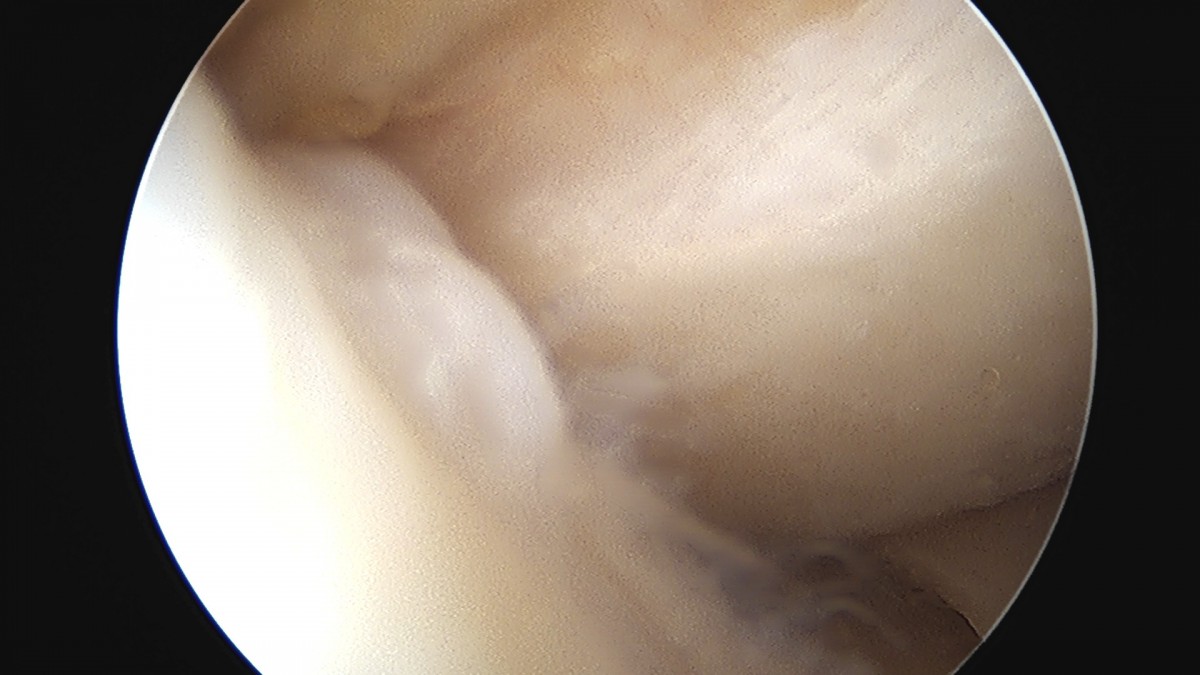

이재상원장님 무릎 반월상 연골판 절제술 홍의O 환자

작성자 최고관리자 댓글 0건 조회 358회 작성일 25-09-16 16:09